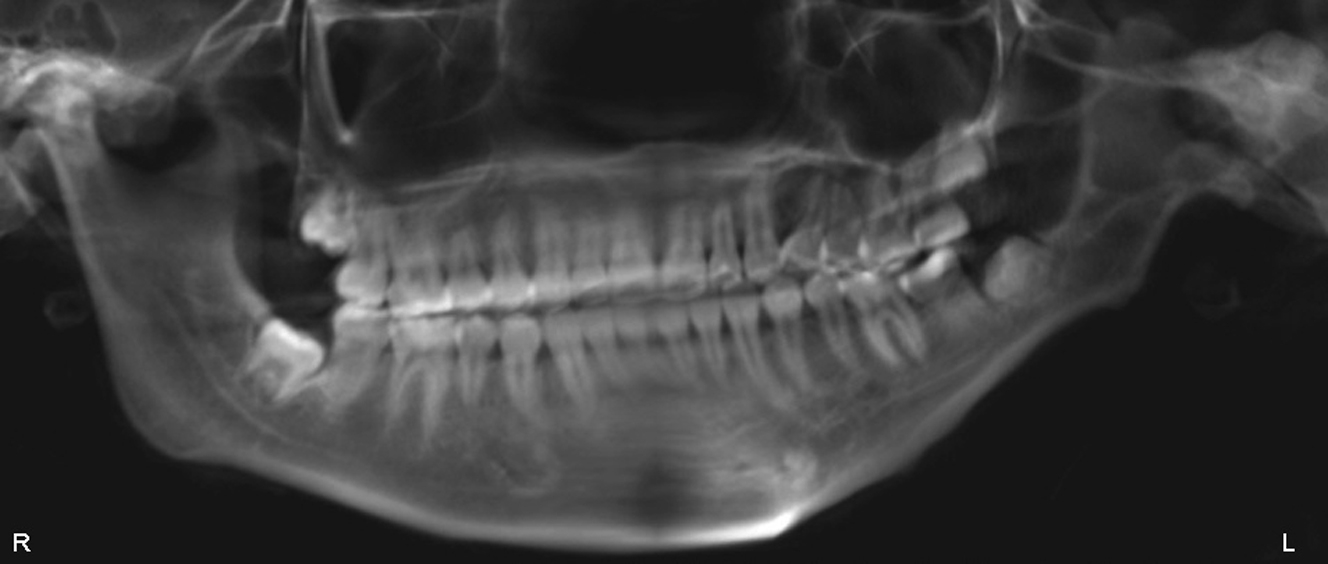

Developing tooth buds

Through 3D surgical planning, orthodontists can idealize device placement to mitigate the negative dental effects of distraction. 3D planning allows visualization of the tooth buds, roots of teeth, and inferior alveolar nerve for proper placement and vector of the distraction device. If extractions are indicated, they should be completed at least 6 months before device placement to avoid damage to the tooth buds or accidental misplacement and to allow sufficient time for bone healing to occur. The tooth buds are not spared in early distraction of the mandible if a mandibular body osteotomy is used. In this case it is usually prudent to extract the second molar tooth buds before treatment. The younger the patient, the more difficult it is to visualize these developing teeth and thus dental injury and future deleterious effects are more likely to occur.